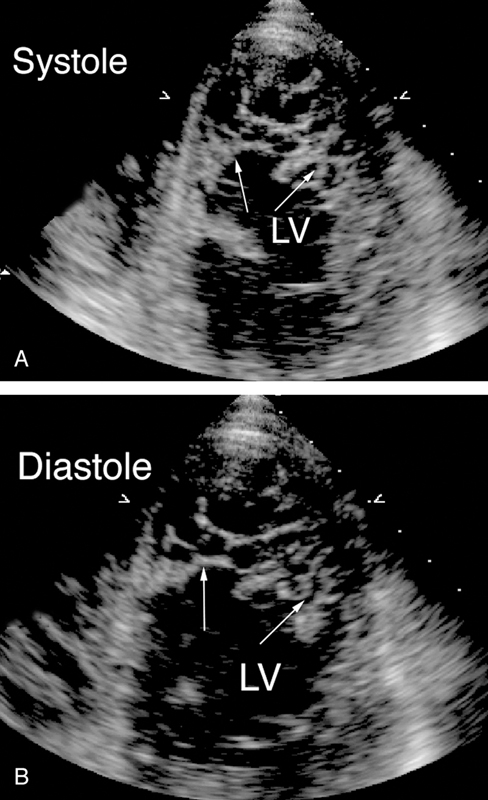

فحوصات تشخيصية لبعض امراض القلب والشرايين التاجية